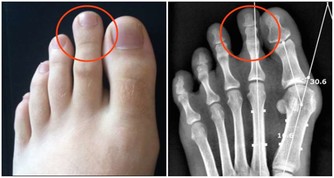

舌癌是第一大口腔癌,也被視為「全球第六高發癌症」,

多好發於抽菸者、牙齒不好者、飲食過辣過燙者。